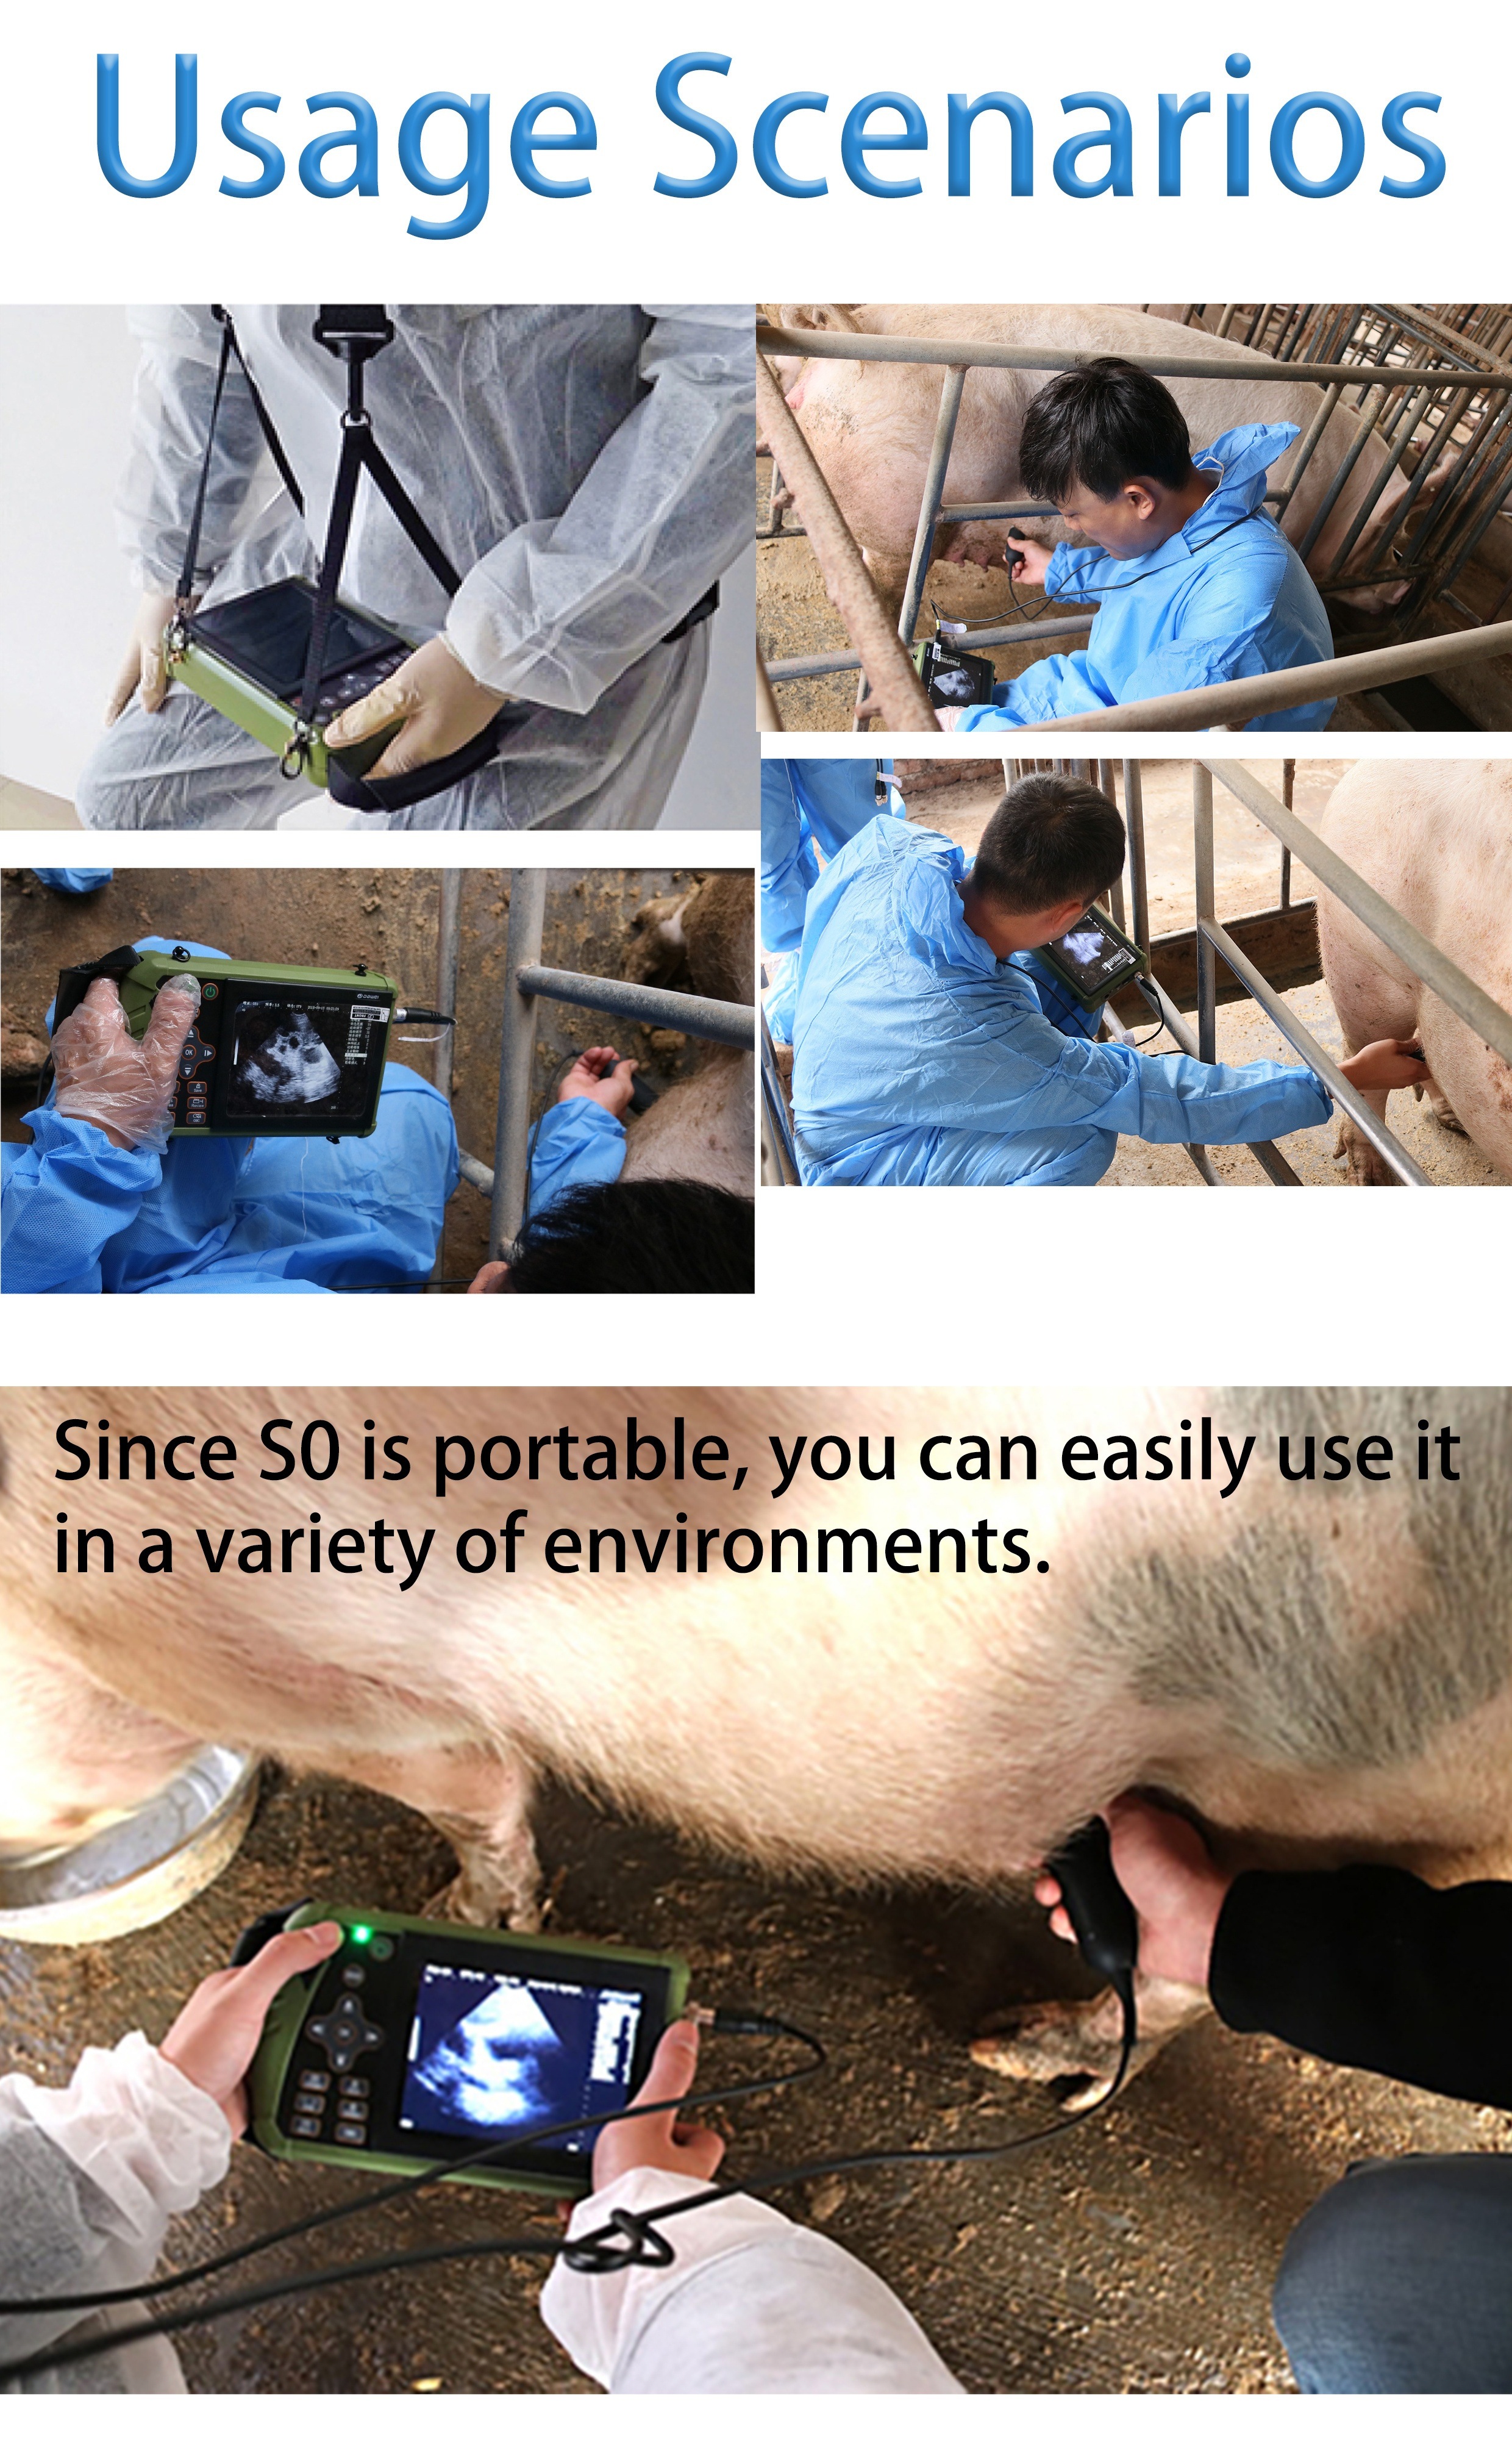

DAWEI-S0 Is A Portable Veterinary Ultrasound (B-ultrasound) Diagnostic Instrument. Its Superior Product Performance And Ergonomic Handheld Design Bring More Convenience To Users During Testing.